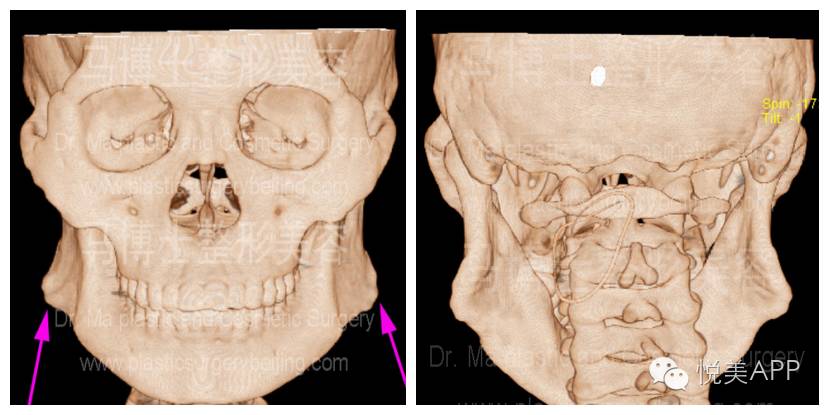

5、在有条件的医院里,还会给换这叫进行三维CT,得到最准确的数据——

可以看到清晰的神经管

▼▼

截骨的范围也看得清清楚楚